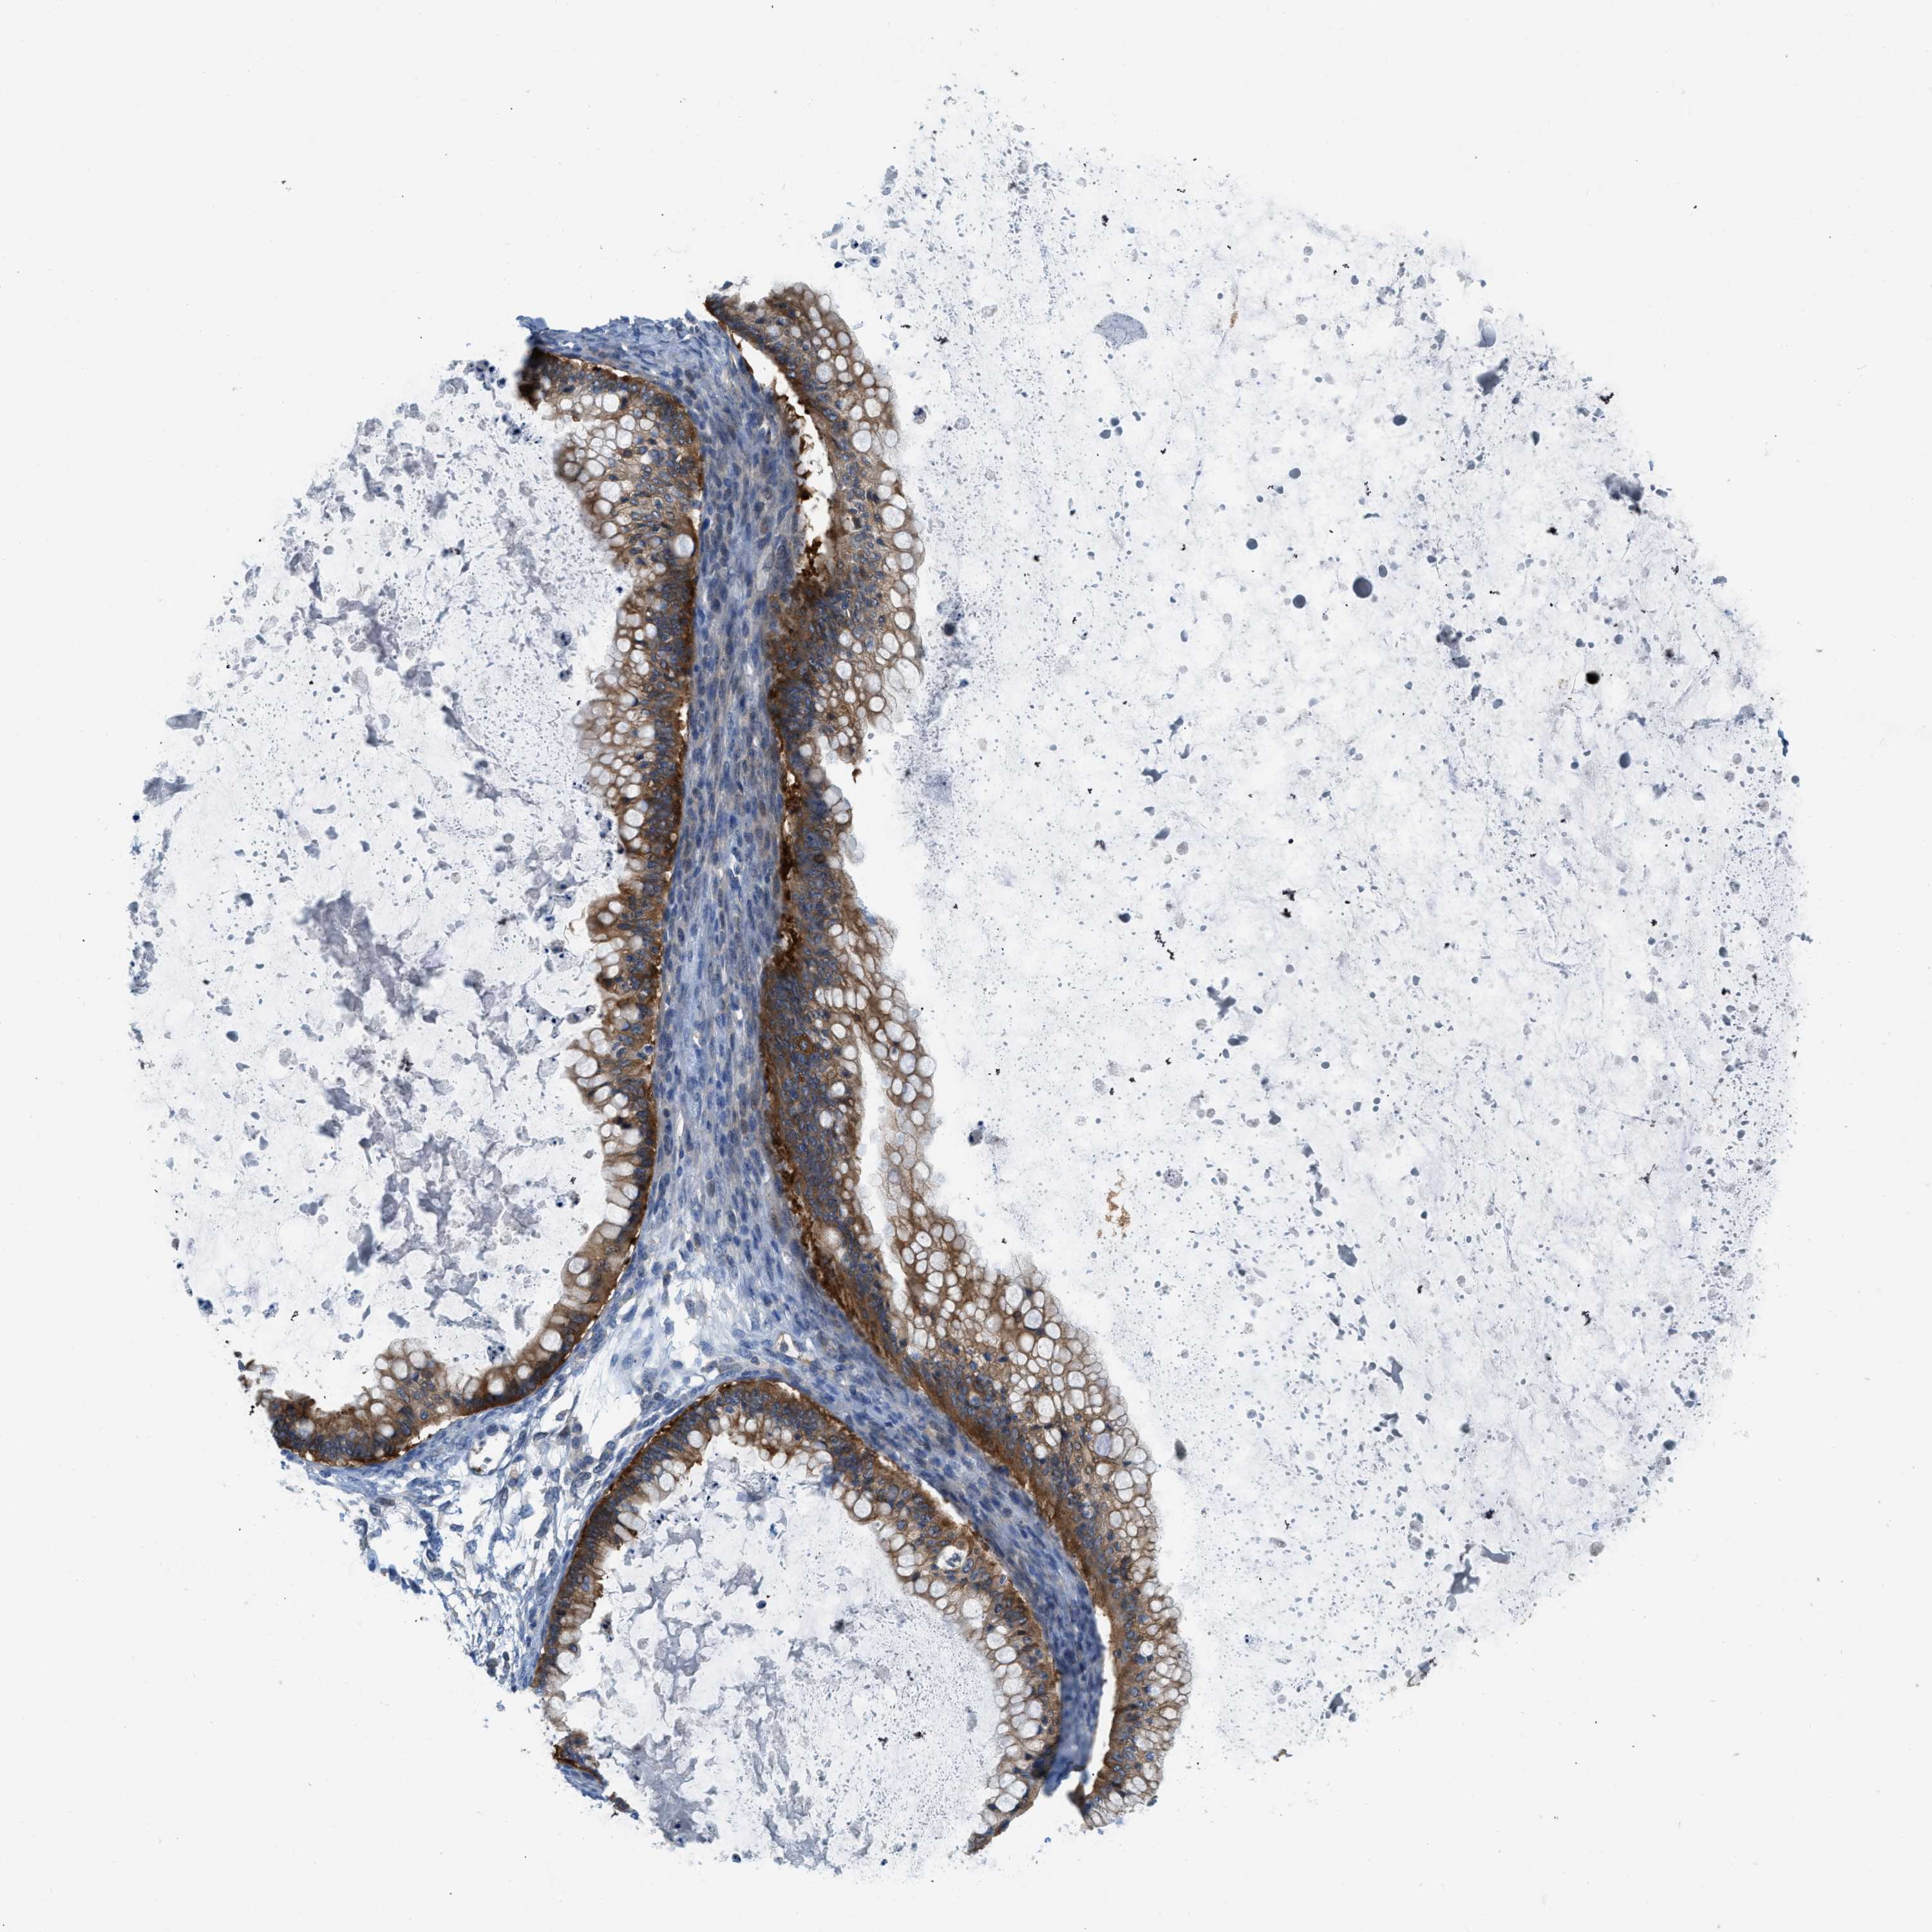

OVARIAN CANCER - Protein expressioni

A mouse-over function shows sample information and annotation data. Click on an image to view it in a full screen mode. Samples can be filtered based on level of antibody staining by selecting one or several of the following categories: high, medium, low and not detected. The assay and annotation is described here.

Note that samples used for immunohistochemistry by the Human Protein Atlas do not correspond to samples in the TCGA dataset.

Antibody stainingi

Antibody staining in the annotated cell types in the current human tissue is reported as not detected, low, medium, or high, based on conventional immunohistochemistry profiling in selected tissues. This score is based on the combination of the staining intensity and fraction of stained cells.

Each image is clickable and will lead to virtual microscopy that enables deeper exploration of all samples and also displays staining intensity scores, fraction scores and subcellular localization as well as patient and tissue information for each sample.

Antibody HPA018257

Staining

High

Medium

Low

Not detected

Intensity

Strong

Moderate

Weak

Negative

Quantity

>75%

75%-25%

<25%

None

Location

Nuclear

Cytoplasmic/membranous

Cytoplasmic/membranous,nuclear

Cystadenocarcinoma, serous, NOS

Carcinoma, endometroid

Cystadenocarcinoma, mucinous, NOS

Carcinoma, NOS